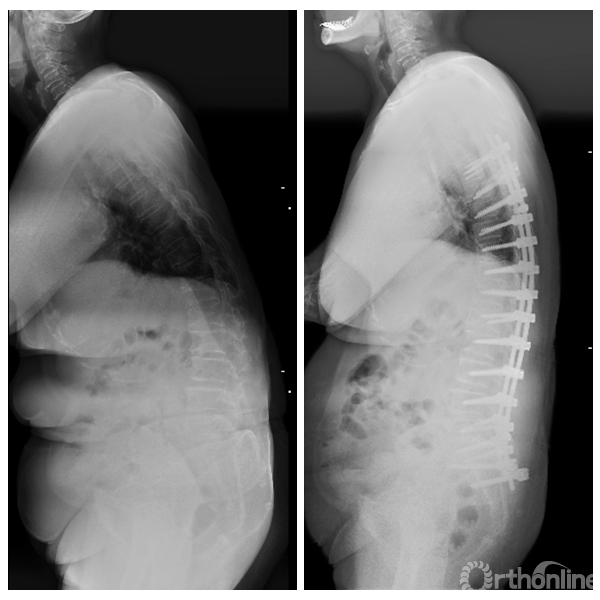

77岁女性,术前PI-LL=52°,SVA=21.7cm,PT=44°,ODI评分64.4,行T6-髂骨后凸矫形术,术后1年随访PI-LL=18°,SVA=7.8cm,PT=27°,ODI评分35.6